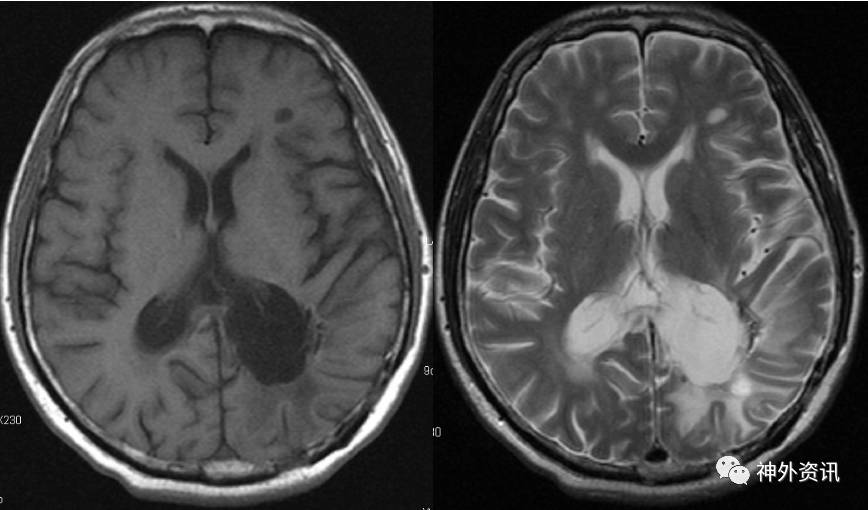

手术顺利,术后予以脱水、激素(甲强龙40mg Qd)及对症支持治疗,患者病情平稳。复查头颅MRI增强(2016.8.22):左侧脑室后角旁不规则形异常信号,呈T1、T2等信号,内见小片T2稍高信号,增强后呈明显强化,强化欠均匀,周边见大片T1低信号、T2高信号水肿区。对比前片(2016-07-12)肿块明显缩小(图6)。

图6. MRI检查:左侧脑室后角旁不规则形异常信号,呈T1、T2等信号,内见小片T2稍高信号,增强后呈明显强化。

出院后1月复查头颅MRI增强示(2016.9.21):左侧脑室后角旁不规则形异常信号,呈T1、T2等信号,内见小片T2稍高信号,增强后呈部分强化。对比前片(2016-08-22)左侧脑室后角及三角部旁病灶明显缩小(图7)。

图7. MRI检查:左侧脑室后角旁不规则形异常信号,呈T1、T2等信号,内见小片T2稍高信号,增强后呈部分强化。